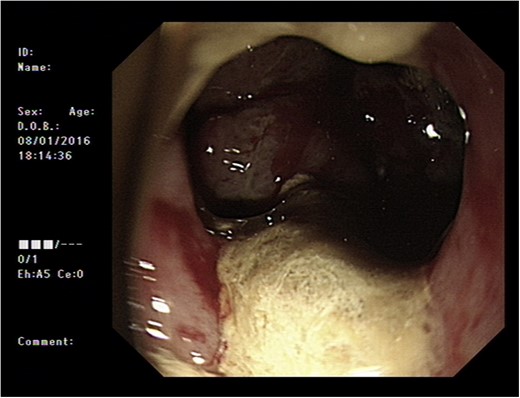

Initial upper GI endoscopy failed to enter the duodenum due to residue within the stomach with the appearance and odour of faeces noted. Abdominal computed tomography (CT) suggested a cavity with adherent ileum adjacent to the second part of the duodenum (Fig. 1). A contrast study was then undertaken demonstrating rapid flow of contrast into the terminal ileum and caecum originating from the duodenum (Fig. 2). Repeat upper GI endoscopy demonstrated an abnormal fungating fistulous communication between the duodenum and terminal ileum which permitted the full insertion of the endoscope (Figs 3 and 4). Biopsies were consistent with diffuse B-cell lymphoma (DLBCL) in accordance with the WHO classification.

Computed tomography image of duodenal-ileal mass (arrow indicates cavity).